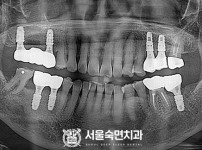

임플란트-전후사진1

임플란트-전후사진2